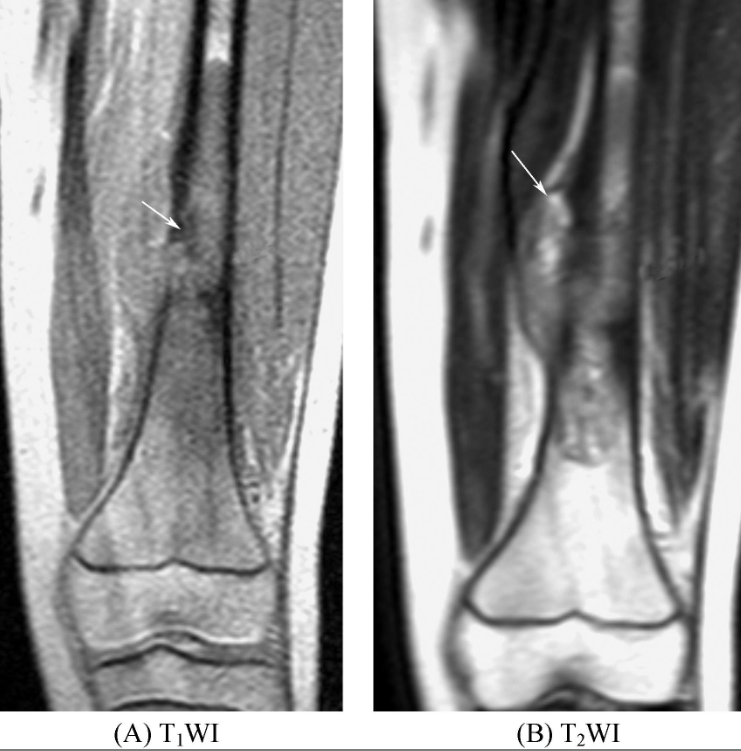

好发于骺板已闭合的四肢长骨骨端,常直达骨性关节面下,表现为膨胀性偏心性骨质破坏。肿瘤边界清楚,周围无低信号环圈。瘤体在T1WI呈均匀的低或中等信号,高信号区提示亚急性或慢性出血。在T2WI信号不均匀,呈混杂信号(图1),瘤组织信号较高,陈旧出血呈高信号,而含铁血黄素沉积呈低信号,出血和坏死液化区可出现液-液平面。一般无骨膜反应。少数可形成骨外肿块,但边界清楚,在T2WI上呈高信号。增强扫描肿瘤组织可见不同程度的强化,而坏死囊变区无强化。

图1 骨巨细胞瘤股骨远端内侧可见类圆形异常信号灶,直达关节面,边界清楚,T1WI上呈不均匀低信号,T2WI上呈高信号,内见多个囊状更高信号影,病变内侧边缘突出骨轮廓,邻近骨皮质不连续。右膝关节腔内可见带状长T1长T2信号影。